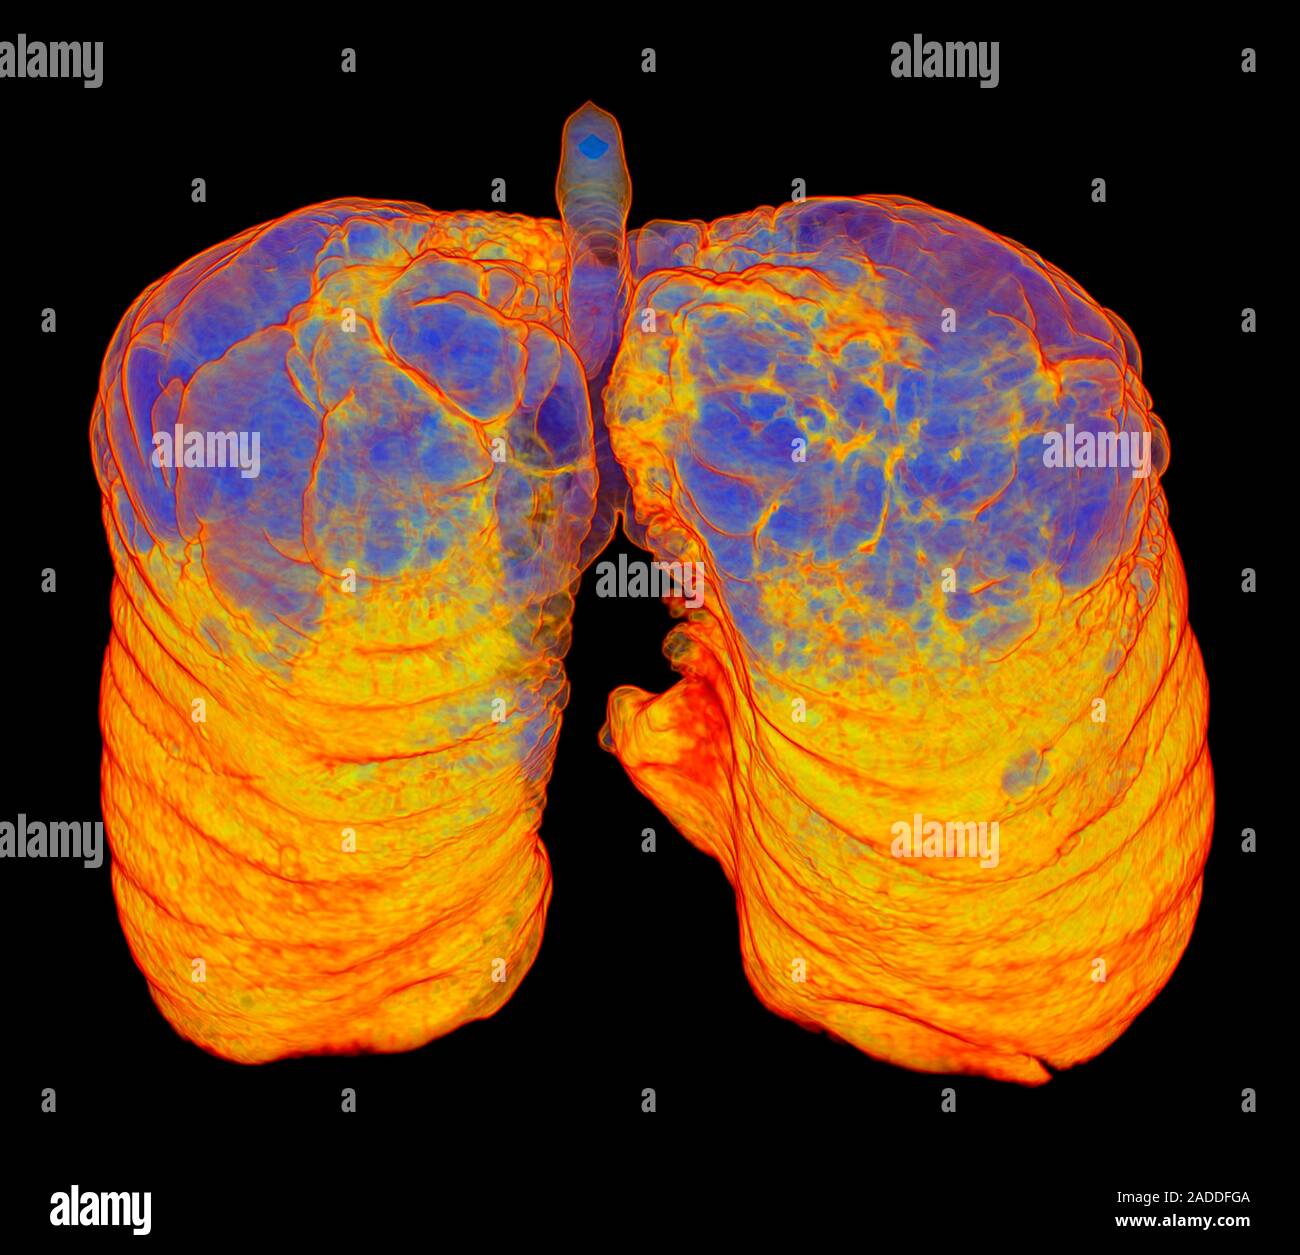

From www.alamy.com

Smoker's lungs and emphysema. Coloured oblique frontal 3D computed Ct Scan Guidelines For Smokers    patients will have their risk of cancer assessed based on their smoking history and other factors and those.  there is evidence that screening people based on their risk of lung cancer can save lives. The initial assessment helps to.   a low dose ct scan helps to check for changes in the lungs that may be lung cancer. Ct Scan Guidelines For Smokers.